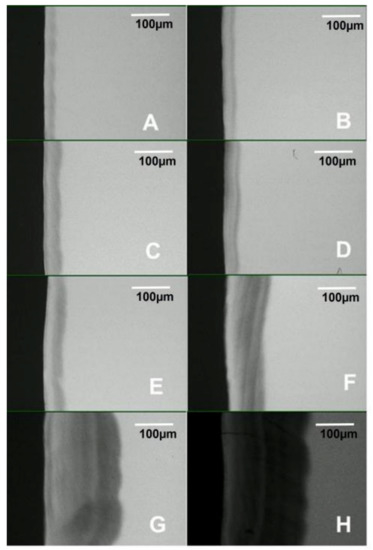

Pearson’s correlation coefficient indicated a strong positive correlation between the biofilm growth time and lesion depth measured with PLM (R2 = 0.9946, p < 0.001) and TMR (R2 = 0.9929, p < 0.001), as shown in Table 1. Also, there was a strong positive correlation (R2 = 0.9908, p < 0.001) between the biofilm growth time and the amount of mineral loss (Table 1). Both the lesion depth evaluated by PLM (Figure 3) and TMR (Figure 4) and the mineral loss (Figure 5) increased with the increase in the length of exposure to biofilm (Table 1). In all these cases, the analyses showed a similar trend of a linear relationship. A similar trend of linear relationship and a strong positive correlation (R2 = 0.9850, p < 0.01) were observed between the lesion depth measured with PLM and that measured with TMR (Table 1). Also, at each measurement time point, there was no significant difference between the lesion depth measured with PLM and that measured with TMR (Table 1). Furthermore, there were no significant differences in lesion depth in samples harvested from day 4 through day 7. Similarly, there were no significant differences in mineral loss in samples harvested from day 4 through day 7.

Examination of the PLM and TMR images shows that the WSL has two layers: a relatively sound surface layer and a subsurface demineralization, and this is more defined at 7 days (Figure 2E) but poorly defined at other time points.

The observation that TMR and PLM lesion depth results showed a strong linear relationship with each other and with the length (time) of caries formation agrees with the reports of a previous study by Ten Bosch and Angmar-Mansson [30]. These established linear relationships would allow estimating the time needed to obtain specifically sized lesions depending on the requirements of any proposed study. PLM images of the lesions after 21 and 28 days of caries formation showed defects such as fractures and cracks below to the outer enamel surface (Figure 2G,H), which could be caused by the excessive exposure time causing extreme demineralization and weakening of the enamel structure. Also, the profile of mineral loss (Figure 5) of these last two assessment time periods showed an irregular lower edge of the lesion body in comparison with lesions from the other time periods. These two conditions could provoke the overestimation of the mineral loss (in these conditions the software translates the internal enamel defects as highly demineralized areas), suggesting that the limit to produce caries lesions with this model would be 14 days, but 7 days for lesions targeted for remineralization study.

Figure 3. Polarized light microscopy images showing the depth and internal structure of caries lesions produced in the artificial mouth model after 3 (A), 4 (B), 5 (C), 6 (D), 7 (E), 14 (F), 21 (G), and 28 (H) days of exposure to biofilm growth. Magnification 450×.